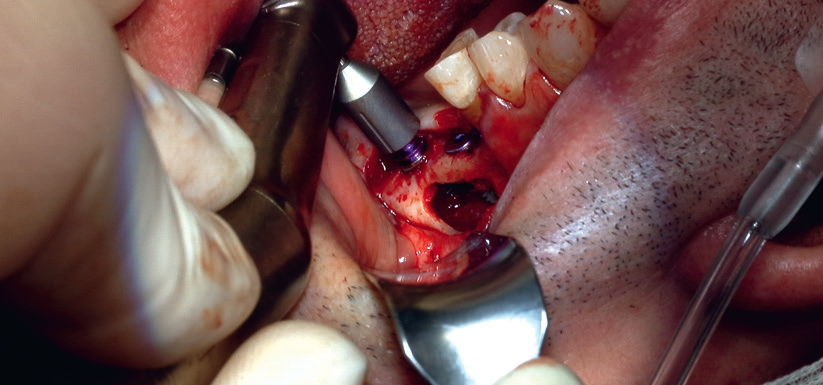

Der Patient stellte sich in unserer Praxis mit Zahnverlust in regio 26 und 27 vor. Trotz extrem dünnem Kieferknochen war eine Versorgung mit Implantaten gewünscht (Abb. 1). Nach konventionellen Standards wäre in diesem Fall ein zweiteiliger externer Sinuslift durchzuführen, bei dem zunächst der Kieferknochen freigelegt und mit körpereigenem und/oder fremdem Knochenersatzmaterial aufgefüllt wird, um nach einer mehrmonatigen Einheilzeit mit der Implantation zu beginnen.

Dieses Vorgehen soll eine feste Verankerung der Implantate sicherstellen, erfordert aber zwei Operationstermine, die wiederum mit einem erhöhten Zeitaufwand verbunden sind. Mit einem weiteren Eingriff gehen darüber hinaus erneut die gängigen Operationsrisiken, zu denen Nerv- und Zahnverletzungen oder Blutungen gehören, und eine erneute Wundheilung einher. Deshalb stellt sich die Frage, ob ein stabiler Halt auch anderweitig zu bewerkstelligen ist.

Im vorliegenden Fall kamen die Piezochirurgie und die Bestimmung des Resonanz-Frequenz-Analyse-Wertes (RFA) zum Einsatz, um Knochenaufbau und Implantation in nur einer Sitzung durchzuführen, ohne die Stabilität des Zahnersatzes zu gefährden (Abb. 2).

Bei dem behandelten Patienten wurde die Schneider-Membran angehoben, um das Knochenaugmentat zwischen dem respiratorischen Epithel der Kieferhöhle und dem Kieferhöhlenboden einzubringen. Hierbei wurde ein Gemisch aus autologem Eigenknochen und xenogenem Knochenersatzmaterial unterhalb der elevierten Kieferhöhlenmembran eingebracht und mit einer resorbierbaren Membran verschlossen, um ein gesteuertes Knochenwachstum (GBR) im augmentierten Bereich zu gewährleisten. Dieser Eingriff erfolgte im Rahmen einer Implantatplanung mit 3D-Technologie, die besonders bei einem dünnen Kieferknochen wichtige Dienste bei der Bestimmung des Restknochenangebots leistet.